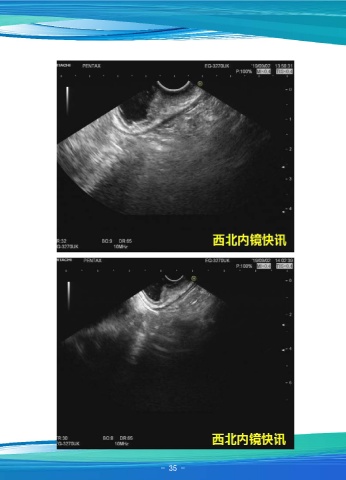

一例贲门早癌

资料提供:张排旗  西安市第三医院消化内科

患者女,68岁,主因“上腹胀痛半月”在外院行胃镜示贲门下方可见一直径约

0.8cm溃疡,上覆薄白苔,病理提示(贲门)低分化腺癌。扇扫超声内镜进镜至贲门,

可见小弯侧片状粘膜粗糙,表面不平。超声内镜显示:粘膜层增厚,回声减低,粘膜肌

层消失,部分病变深达粘膜下层深层,最厚处5.9mm。固有肌层完整连续。壁外未见腹

水征及明显肿大淋巴结。诊断:贲门癌(T1N0Mx)(sm2-sm3)。